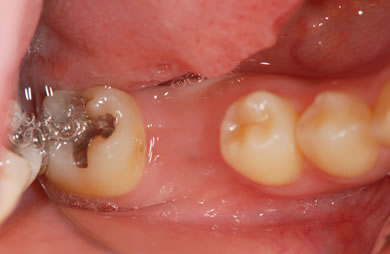

インプラントの症例写真 IMPLANT

骨再生インプラント治療+セラミック治療

| 治療方針 | 左側の奥歯の部分の歯が欠如しているのでインプラント治療にて機能的・審美的回復を行いつつ、その他の虫歯の部分はセラミック歯にて治療を行う。 | ||||||||||||||||||||||||||||||||

| 治療内容 | インプラント2本(ソケットリフト)、ハイブリッドセラミック2本、オールセラミック3本(オールセラミック用の土台3本)、メタルボンドセラミック2本(メタルボンドセラミック用の土台1本) | ||||||||||||||||||||||||||||||||